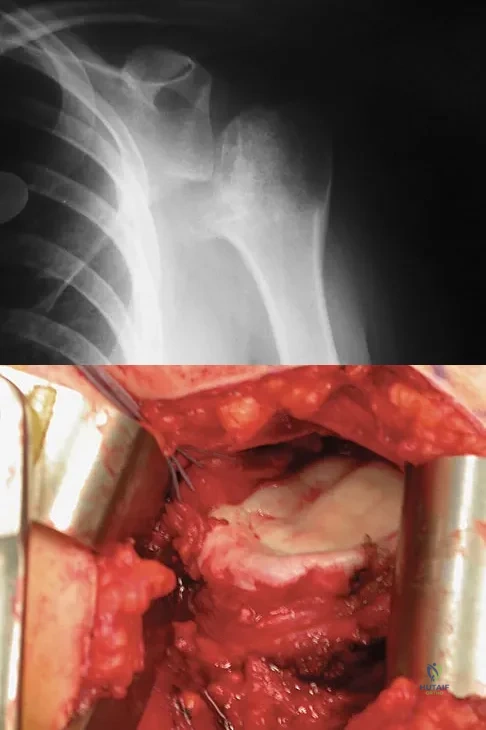

Question 22

A 28-year-old man sustained a shoulder dislocation 2 years ago. It remained dislocated for 3 weeks and required an open reduction. He now reports constant pain and has only 60 degrees of forward elevation and 10 degrees of external rotation. He desires to return to some sporting activities. An AP radiograph and intraoperative photograph (a view of the humeral head through a deltopectoral approach) are shown in Figures 31a and 31b. What is the best treatment option to decrease pain and improve function?

Explanation